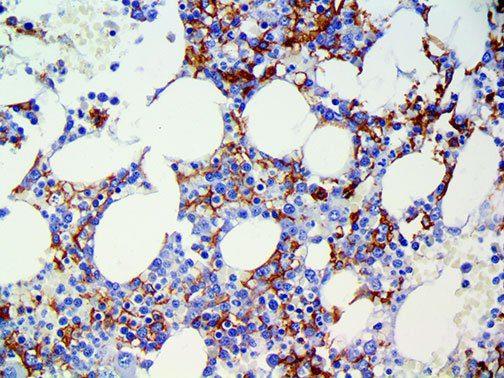

Clinical and laboratory manifestations of HLH include fever, enlarged liver and/or spleen, neurologic dysfunction, coagulopathy, liver dysfunction, cytopenias (i.e., low levels of erythrocytes, leukocytes, and/or platelets), hypertriglyceridemia, hyperferritinemia, hemophagocytosis, and eventually diminished NK cell activity as the immune system becomes progressively paralyzed. HLH can be familial (primary HLH) or secondary to another disease process (sHLH), such as rheumatic disease, in which it is referred to as macrophage activation syndrome (MAS, characterized by elevated ferritin).

This activation induces inflammatory monocytes to highly express IL-6, starting a localized and then systemic cascade effect that results in hyperproduction of IL-6, which accelerates the inflammatory process. Because IL-6 also increases vascular permeability, excessive levels cause blood vessels to become very leaky. This, along with clotting factors released from vascular endothelial cells, stimulates the coagulation cascade, resulting in microthrombosis (tiny clots), which leads to ischemia and tissue death of the kidney, intestines, heart, liver, brain and extremities.